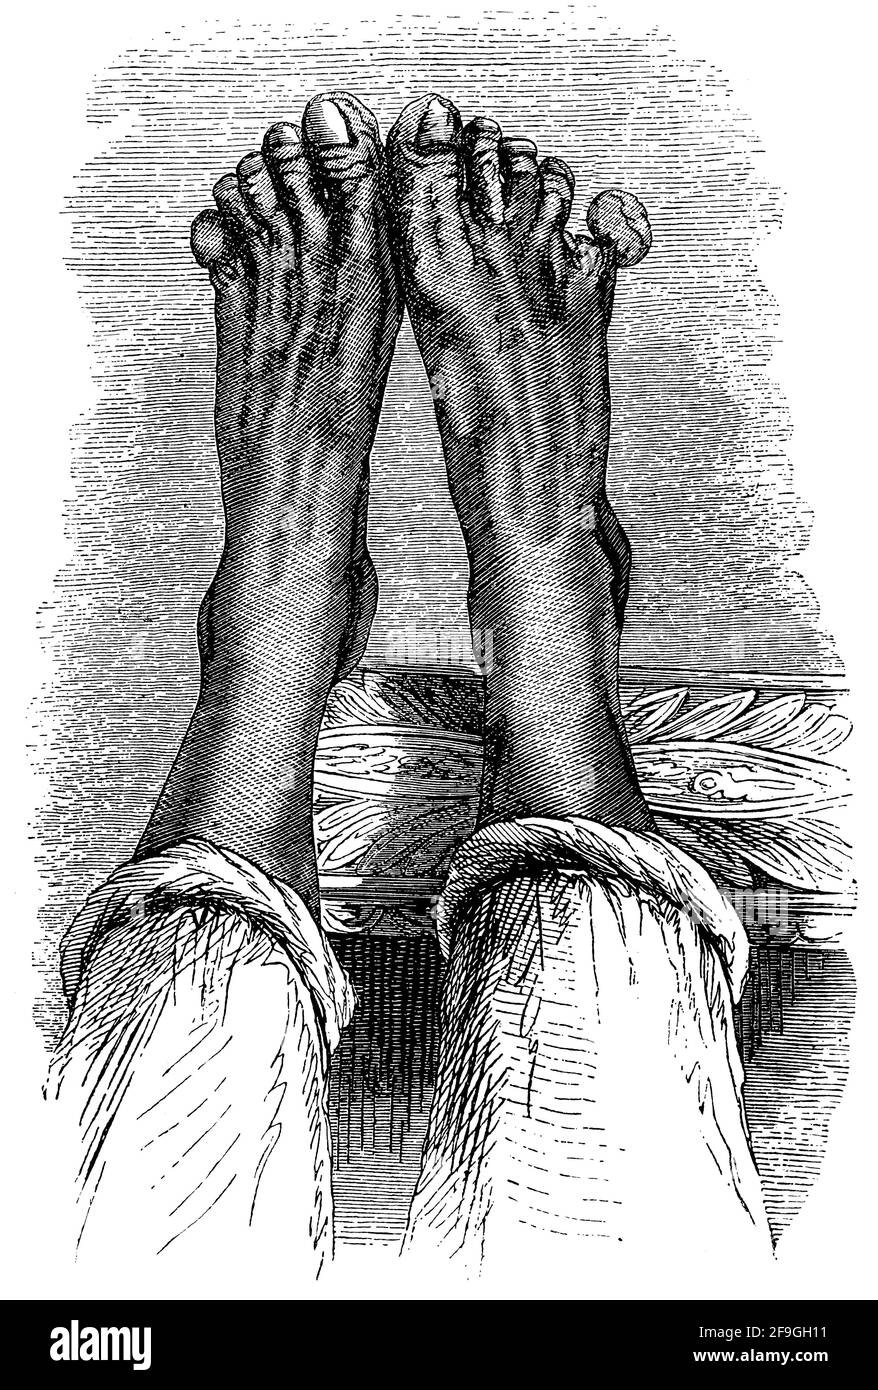

RMCRKB8M–Nahaufnahme von einer Sepsis Ischämie Oberschenkel. Ischämie ist die eingeschränkte Blutversorgung zu einem Bereich des Körpers, durch die Verengung der Blutgefäße verursacht. In diesem Fall hat Ischämie verursacht den Tod von Gewebe und Infektion.

RMCRKB90–Nahaufnahme von einer Sepsis Ischämie Oberschenkel. Ischämie ist die eingeschränkte Blutversorgung zu einem Bereich des Körpers, durch die Verengung der Blutgefäße verursacht. In diesem Fall hat Ischämie verursacht den Tod von Gewebe und Infektion.

RMCRKB9H–Nahaufnahme von einer Sepsis Ischämie Oberschenkel. Ischämie ist die eingeschränkte Blutversorgung zu einem Bereich des Körpers, durch die Verengung der Blutgefäße verursacht. Das Hautgewebe wird zu sterben beginnt und schnell beschädigt und infiziert wenn nicht behandelt.

RMCRKBA8–Nahaufnahme von einem erhöhten Sünde ein Patient leidet Ischämie. Ischämie ist die eingeschränkte Blutversorgung zu einem Bereich des Körpers, durch die Verengung der Blutgefäße verursacht. Das Hautgewebe wird zu sterben beginnt und schnell beschädigt und infiziert wenn nicht behandelt.

RM2BFDYX2–Nahaufnahme einer Sepsis ischämia Oberschenkel. Ischämie ist die eingeschränkte Blutversorgung eines Körperbereichs, verursacht durch die Verengung der Blutgefäße. Die s

RMCRKBB4–Ein 52 Jahre alter Mann hat die Wunde seines amputierten rechten unteren Extremität beseitigt. Er verlor sein Bein durch vorherige Ischämie (Einschränkung der Blutversorgung).